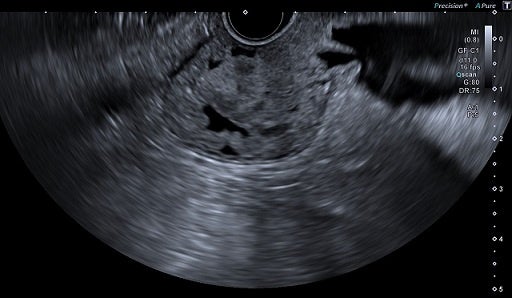

EUSでは超音波画像の濃淡の差を見ることが大切です。キヤノンメディカルが開発したD-THI (Differential Tissue Harmonic Imaging)では浅部から深部にかけて十分な感度を持つ高分解能な映像を得ることが可能で、組織内部や境界エコーの描出能が向上します。これにより腫瘍、のう胞などの病変と正常組織の識別が素早く行え、診断・治療をサポートします。

D-THI